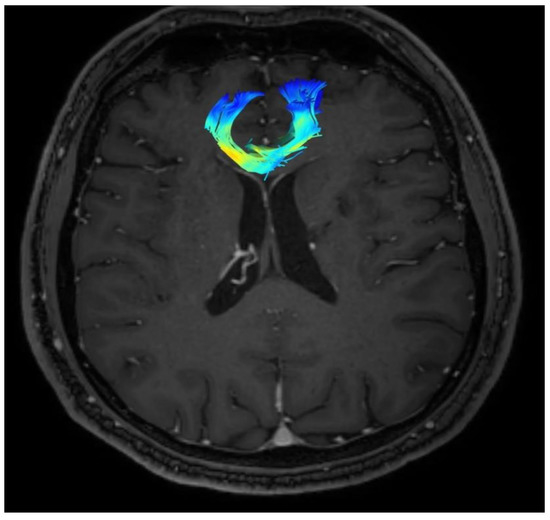

In the presented case, the analysis covered forceps minor and arcuate fasciculus. The following parameters were used for the purpose of the evaluation: FA, ADC, MD, and the number of fibers. The parameters were measured immediately before the procedure and six months after the cingulotomy. Their exact values are presented in Table 1 and Table 2.

Based on the collected results, after 6 months follow up, an increase in the FA value of both the forceps minor and both the arcuate fasciculus was noted. Moreover, an increase in the number of fibers was observed in each analyzed structure, compared to the initial results.

Changes in the anatomy of forceps minor before and after cingulotomy are presented in Figure 2 and Figure 3; moreover, arcuate fasciculus before and after cingulotomy is presented in Figure 4 and Figure 5.

Figure 3. Forceps minor after cingulotomy.

Brainsci 13 00044 g003